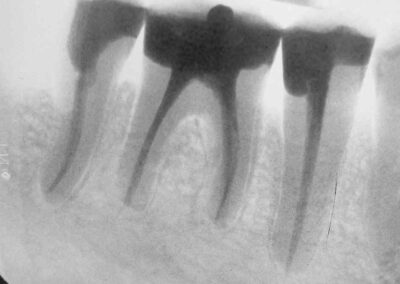

Ganz besonders „beweiskräftig“ sind in unseren Augen jedoch Fälle, bei denen im selben Gebiss gleichzeitig mehrere apikale Ostitiden vorliegen, die alle zur Ausheilung gebracht werden. Auch solche Fälle konnten wir mehrfach vorstellen. Hier ist ein weiterer.

Er zeigt in beeindruckender Weise, dass die Ausheilung apilaler Ostitiden routinemäßig abläuft, voraussagbar erfolgreich ist, keinerlei Geheimnis beinhaltet und keine besonders aufwendige, teure technische Gerätschaft, sondern lediglich eine ordentliche Aufbereitung der Wurzelkanäle und die sorgfältige Desinfektion aller infizierter Bereiche erfordert. Kritiker unserer Methode behaupten gerne, dass die Regression der Aufhellung schon durch eine leichte Veränderung im Strahlengang oder durch eine nur leicht unterschiedliche Filmschwärzung vorgetäuscht werden könne. Zum Glück gibt es in diesen modernen Zeiten nicht nur das Internet, um die Bilder zeigen zu können, sondern auch das elektronische Verfahren der Bildinversion, das den nachhaltigen optischen Beweis für die röntgenologisch knochendichte Ausheilung des Granuloms liefert, und in der Folge dafür, dass es sich weder um eine ungewollte, noch eine beabsichtigte Täuschung handelt.